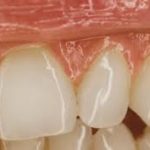

Diş Eti Çekilmesi: Nedenleri, Mekanizmaları ve Önleme Yöntemler Diş eti çekilmesi (gingival retraksiyon), dişeti dokusunun diş kökünden geri çekilmesiyle karakterizedir. Bu durum yalnızca estetik sorun yaratmakla kalmaz, aynı zamanda diş kökünün açığa çıkması nedeniyle hipersensitivite, çürük riski ve periodontal hastalık progresyonu gibi komplikasyonlara yol açabilir. Çekilmenin oluşumunda hem mekanik hem de biyolojik faktörler rol oynar.

- Periodontitis: Dişeti ve alveolar kemiğin kaybına yol açan ileri inflamasyon, diş eti çekilmesinin en yaygın biyolojik nedenidir.

- Periodontal cep oluşumu ve kemik kaybı, dişetinin diş kökü üzerinden geri çekilmesini kolaylaştırır.